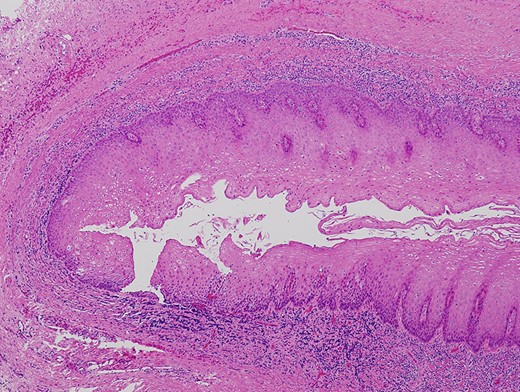

A 66-year-old man was referred to our institution in January 2018 for the diagnosis and treatment of a right buccal lesion. The lesion was first noticed approximately 1 month previously during an examination by his family dentist. The patient’s medical and family histories were unremarkable. He had no history of trauma to the face. Physical examination revealed bruising on the skin of his right cheek (Fig. 1). In the oral cavity, a mucosal outpouching (5-mm diameter, 10-mm depth) was observed in his right cheek. Food debris was seen in the outpouching (Fig. 2). The adjacent overlying oral mucosa was normal in appearance. The clinical diagnosis was a diverticulum-like lesion of the buccal mucosa. Excision of the outpouching was performed through an intraoral incision to stop food impaction (Fig. 3). It was easily separated from the surrounding soft tissues and completely excised (Fig. 4). The bottom of the outpouching was over the buccinator muscle on the lateral side. The buccinator muscle layer and oral mucosal layer were sutured separately. Histopathological examination revealed that the excised lesion was a true diverticular structure composed of a keratinising, squamous epithelial lining with a surrounding fibrous connective tissue wall, with inflammatory cell infiltration and haemorrhage (Fig. 5). In contrast to the normal buccal mucous epithelium, the diverticular epithelium had a thick stratum spinosum appearance with formation of anastomosed rete ridges (Fig. 6). The surface of the parakeratinised epithelium was corrugated. The histopathological diagnosis was a diverticulum of buccal region. The postoperative course was uneventful.

Histopathologic findings of the lesion revealed a true diverticulum composed of an inner layer of squamous epithelium and an outer layer of fibrous connective tissue (haematoxylin–eosin stain, ×5).